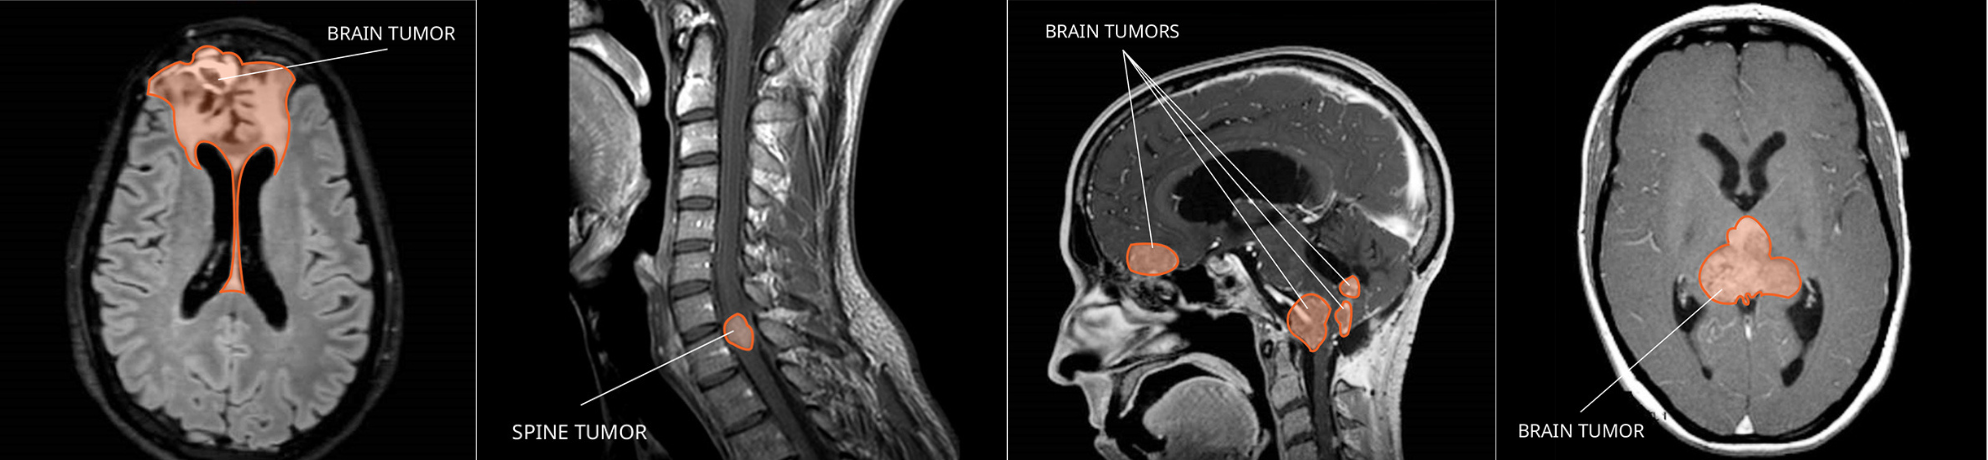

Rare Brain and Spine Tumors

Primary central nervous system (CNS) tumors begin in the brain or spinal cord. There are over 130 different CNS tumor types. However, they account for less than 2 percent of all cancers diagnosed each year in the United States. For more statistics, visit the NCI Surveillance, Epidemiology, and End Results Program website.

Because primary CNS cancers are so rare, disease information, support, and expert care can be hard to find. NCI-CONNECT started with 12 select tumor types, each with fewer than 2,000 people diagnosed per year in the United States. It has since expanded its selection to include tumor subtypes based on molecular findings—and will continue to do so as new discoveries are made. Explore these NCI-CONNECT resources to learn about CNS anatomy, as well as CNS tumor causes, symptoms, diagnosis, and treatment.